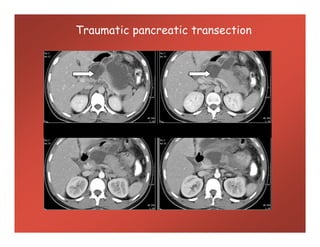

Traumatic pancreatic transection